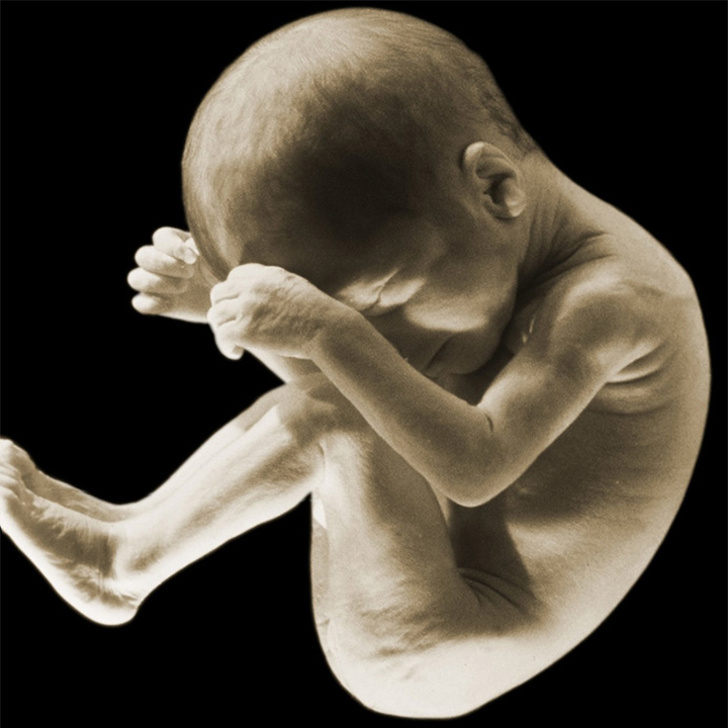

Дитина на 30-му тижні вагітності.

Шар підшкірного жиру збільшується, і малюк стає все більш пухким і вгодованим. Крім того, він вже вміє плакати, кашляти і навіть іноді гикає — відбувається це, швидше за все, тоді, коли він заковтує занадто багато навколоплідної рідини. До 30-му тижні мозок дитини вже настільки розвинений, що він цілком здатний запам'ятовувати і навіть аналізувати інформацію.